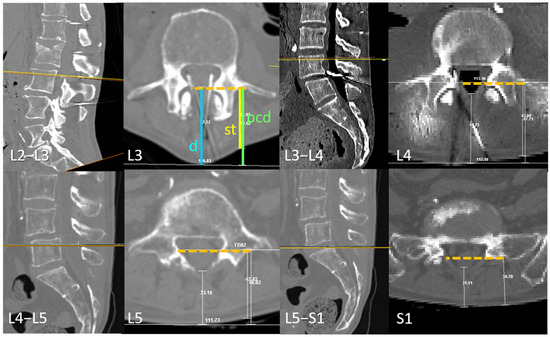

Open AccessArticle

by

Anna Puigdellívol-Sánchez, Hipólito Labandeyra, Alberto Prats-Galino and Xavier Sala-Blanch

NeuroSci 2025, 6(4), 119; https://doi.org/10.3390/neurosci6040119 - 21 Nov 2025

Background: The skin-to-transverse process distance (st) correlates with the skin-to-dural sac depth (d) and may be used to estimate optimal angles for perpendicular needle insertion using the formula inverse cosine d/√(1 + d2), as outlined in free visual guides. Objective: We

Background: The skin-to-transverse process distance (st) correlates with the skin-to-dural sac depth (d) and may be used to estimate optimal angles for perpendicular needle insertion using the formula inverse cosine d/√(1 + d2), as outlined in free visual guides. Objective: We aimed to analyze the relationship between the transverse process and dural sac depth at lumbar levels relevant to spinal anesthesia and to determine the range of planes where perpendicular paramedian needle insertion is feasible when midline access is not viable. Methods: Ten ex vivo trunks were flexed using an abdominal support, and CT scans were performed. Correlations between the transverse process and dural sac depth were evaluated from L3 to S1. Perpendicular planes at the level of needle paths were examined at L3–L4 and L4–L5. Median path viability was assessed. Results: The transverse process aligned with the dorsal dural sac at L3, the posterior third at L4, and the middle zone at L5 or S1. Median needle insertion was not viable in 20–30% of L4–L5 and L3–L4 levels, respectively. However, paramedian access was possible. The vertical range of viable paramedian planes was 8.7 ± 2.9 mm (L4–L5) and 7.9 ± 1.9 mm (L3–L4). Coronal reconstructions showed that the upper level of the transverse process correlates with the skin-perpendicular planes where insertion is likely to succeed. Conclusion: Many elderly spines lack viable midline paths. The superior aspect of the transverse process serves as a useful landmark for estimating dural sac depth, calculating paramedian angles, and identifying the plane for successful perpendicular needle insertion.

Figure 1